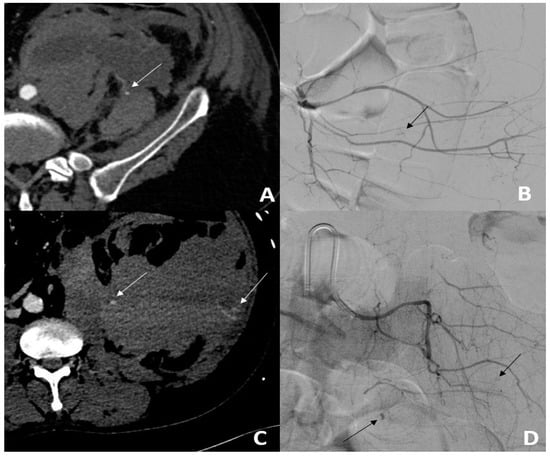

Angiographic active bleeding was detected in 50/56 (89.3%) patients, resulting in 6/56 (10.7%) patients being treated by empiric TAE. Procedures were performed using a gelatine sponge for 32/56 (57.2%) patients, microparticles for 11/56 (19.6%) patients; N-Butyl Cyanoacrylate (NBCA) for 4/56 (7.1%), with a combination of sponge and microparticles for 2/56 (3.6%) patients; a combination of gelatine sponge and NBCA in 1/56 (1.8%) patients; and a combination of coils, gelatine sponge, and particles for 1/56 (1.8%) patients (Figure 1).

The main arteries embolized were: the lumbar artery in 30/56 (53.6%) patients, the inferior epigastric artery in 15/56 (26.8%) patients, and the ilio-lumbar artery in 14/56 (25.0%) patients. Multiple arteries were embolized in 8/56 (14.3%) patients. Two hematomas at the puncture site were reported (Grade A). Pre-procedure data are detailed in Table 3.

Figure 3. Back pain in a 45-year-old patient hospitalized for Sars-cov2 infection and pulmonary embolism. (A) The MDCT scan showed active bleeding (white arrow) from a large left retroperitoneal hematoma. (B) Angiography confirmed active unifocal bleeding (black arrow) from the left L5 lumbar artery, treated with gelatine sponge (C). On day 1, the patient presented with persistent blood loss. The MDCT scan showed a persistent hematoma with active bleeding (white arrows). (D) Angiography showed new multifocal active bleeding (black arrows) treated using 1 coil.